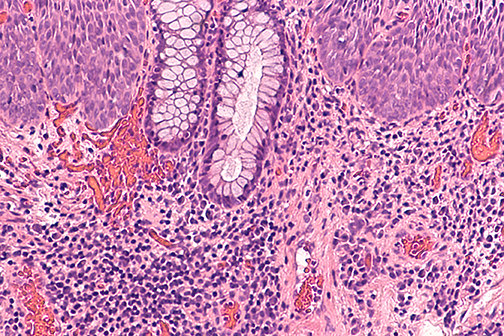

Study Finds Treating Precancerous Growths in People with HIV Reduces Anal Cancer by More Than Half

A team of researchers, including LSU Health New Orleans Infectious Diseases and Microbiology professor Michael Hagensee, MD, PhD, has shown for the first time that treating precancerous anal growths called high-grade squamous intraepithelial lesions (HSILs) in persons living with HIV significantly decreased the progression to anal cancer. Results are published in the New England Journal of Medicine. More